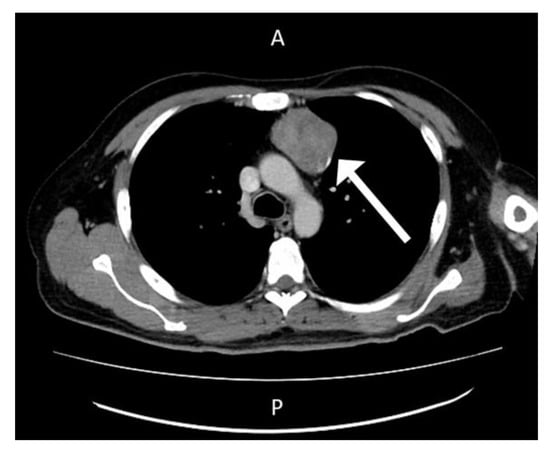

The patient was admitted to the division of rheumatology for suspected partially treated reactive arthritis. Blood tests revealed a white blood cell count of 11,330 cells/mm3, hemoglobin level of 9.0 g/dL, platelet count of 639,000 cells/mm3, creatinine level of 0.6 mg/dL, ALT level of 20 U/L, AST level of 124 U/L, CRP level of 24.27 mg/L, ferritin level of 3408 ng/mL and erythrocyte sedimentation rate of 117/h. Again, microbial examinations of sputum, blood, urine, and feces did not identify any pathogens. Blood sampling did not detect any autoantibodies. Cardiac echo–Doppler revealed no vegetation at the cardiac valves. Sonography of whole abdomen revealed coarsening echo-pattern which was suspected to be fatty liver disease related. Based on the examination protocol for fever with unknown origin [6], computed tomography scans with contrast of the chest showed a mass lesion in the anterior mediastinum and enlarged lymph nodes (Figure 3).

Figure 3. Computed Tomogram Scan with contrast at Chest revealed mass lesion over anterior mediastinum region.